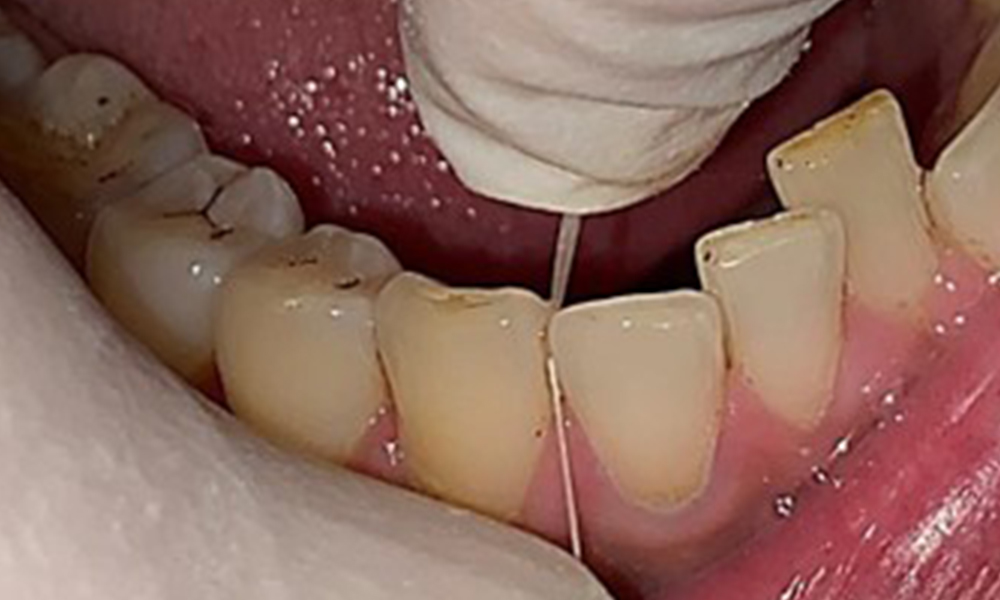

Observații la nivel dentar

Pacientul prezintă o dentiție completă, cu 28 de dinți. Se remarcă eroziuni și atriții. (Fig. 4, Fig. 5). Datorită bruxismului, timp de mulți ani, pacientul a purtat gutieră pe timp de noapte. Eroziunile sunt cauzate de consumul prelungit de băuturi izotonice. Nu au fost observate pierderi osoase de natură parodontală sau carii active.